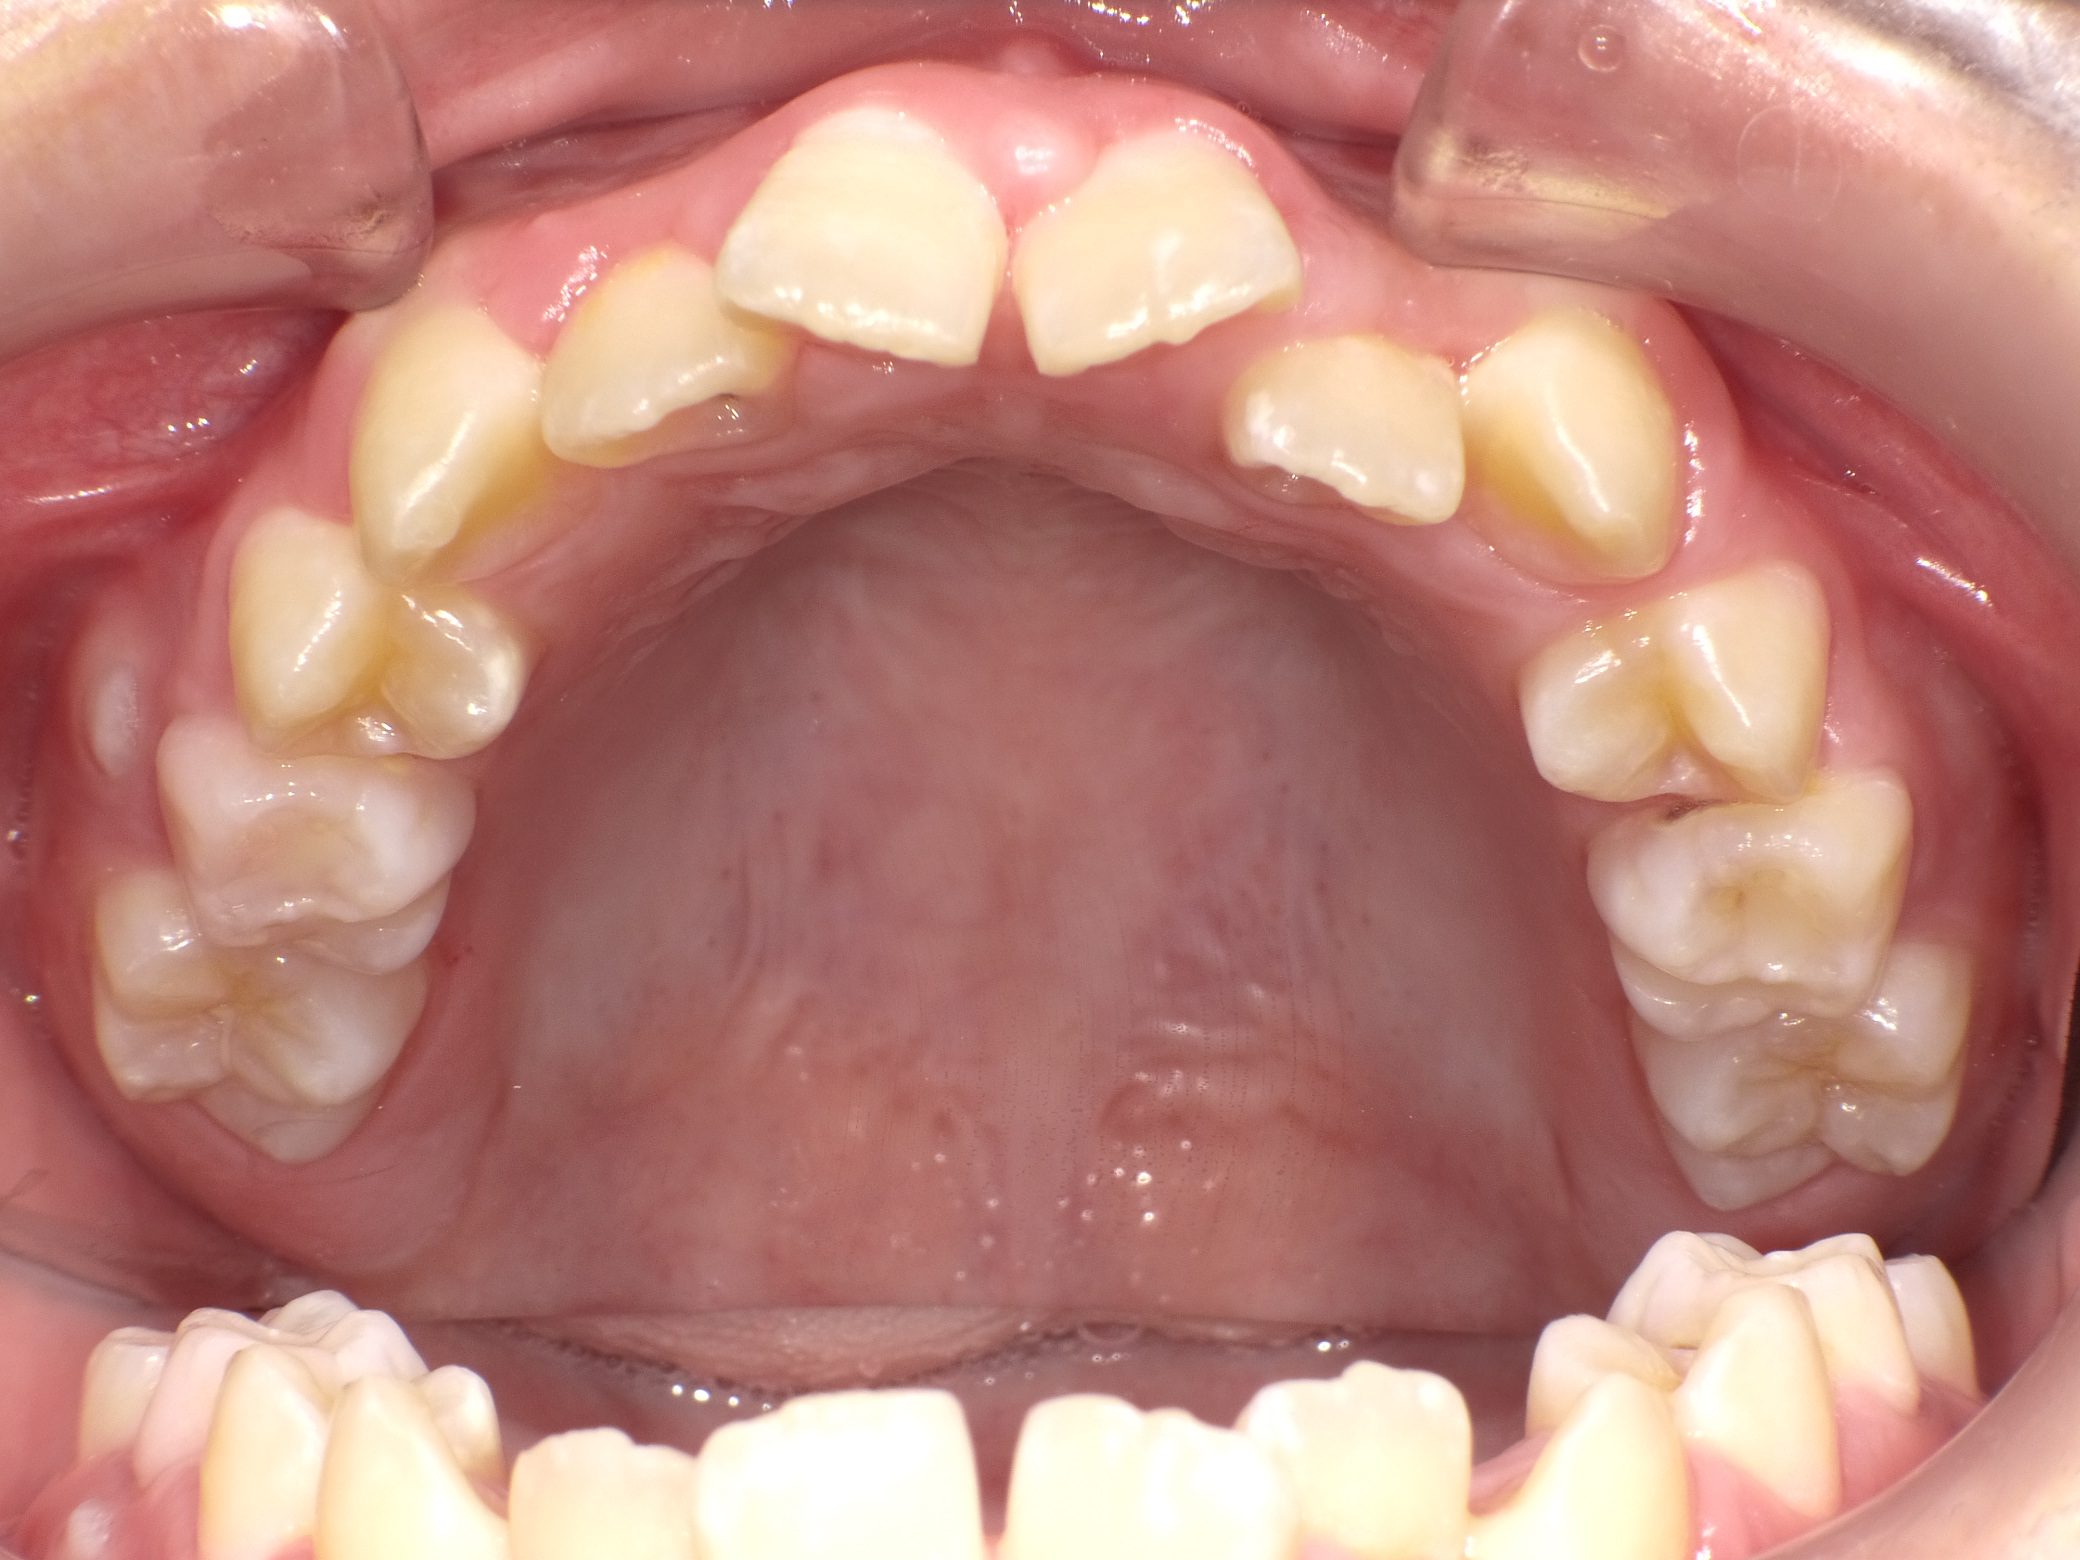

【小学生】マイオブレース矯正 受け口を改善 ①

小学生で開始

マイオブレース

受け口

1期治療のみで改善

Before

After

治療期間

1年11カ月年

治療開始

10歳

種類

マイオブレース矯正

使用装置

機能矯正装置

コメント

毎日装置の装着と MFT 口腔筋機能療法 に取り組んでくれたためスムーズに終わりました。

上顎前歯の並びをもう少し別の装置で改善することも提案しましたが、本人、保護者の方ともに

今の歯並びで満足しているということだったのでこれで終了しています。

MFTを頑張ってくれたため、お口の筋肉バランスもよく、後戻りもしていません。